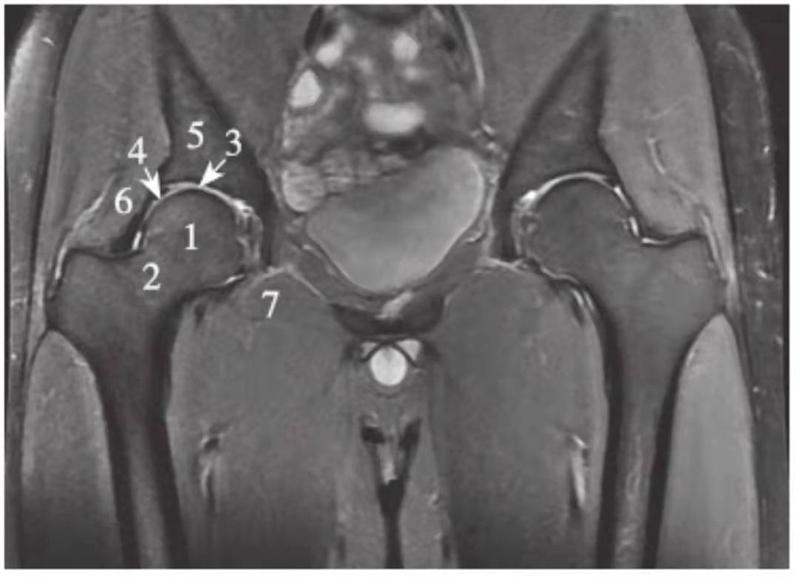

冠状位

正常髋关节经股骨头中心层面T1WI像

1.股骨头;2.股骨颈;3.髋臼窝内脂肪;4.髂骨;5.臀小肌;6.臀中肌;7.闭孔内肌;8.闭孔外肌;9.股外侧肌;10.股内侧肌

正常髋关节经股骨头中心层面T2WI像

1.股骨头;2.股骨颈;3.大转子;4.髂骨;5.臀小肌;6.臀中肌;7.闭孔内肌;8.闭孔外肌;9.股内侧肌;10.股外侧肌